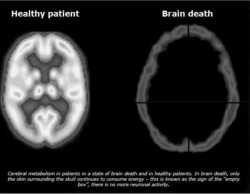

>>520522390